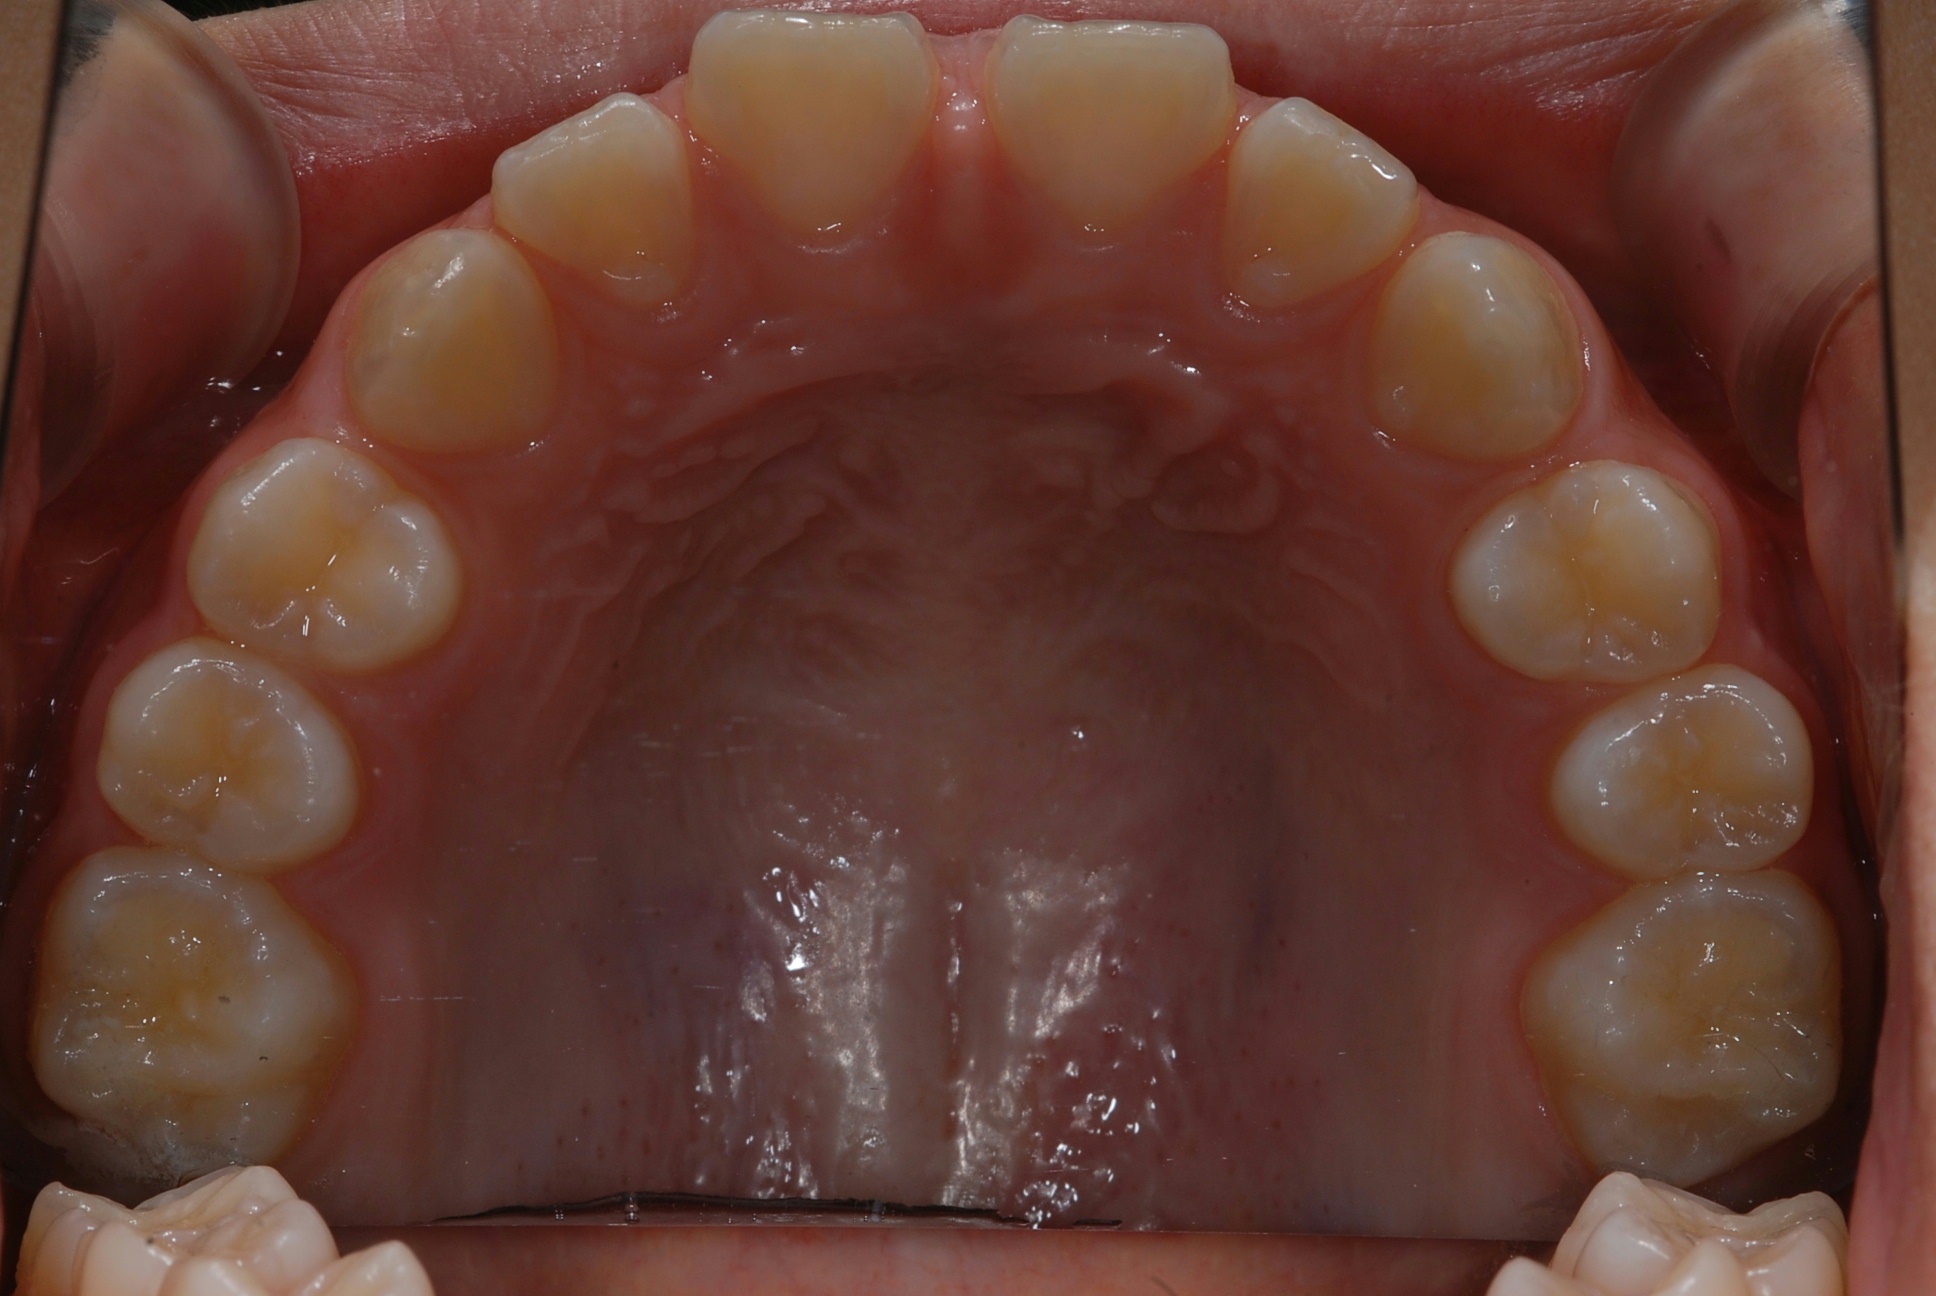

치료 전 사진입니다.